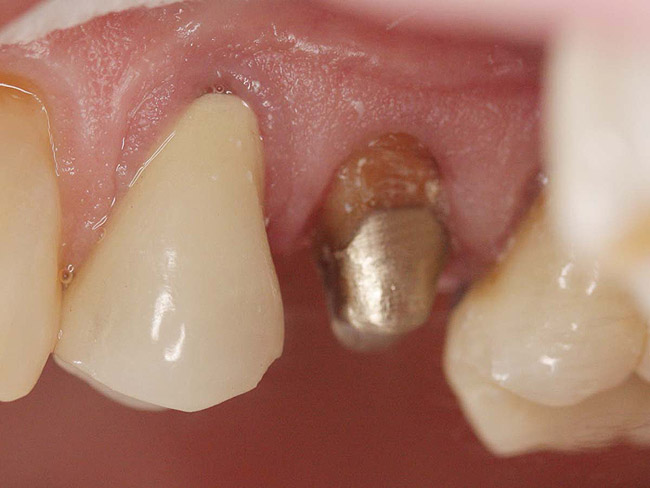

Figure 2  Same second bicuspid as Figure 1 after removal of the fractured fiber post.

Figure 2